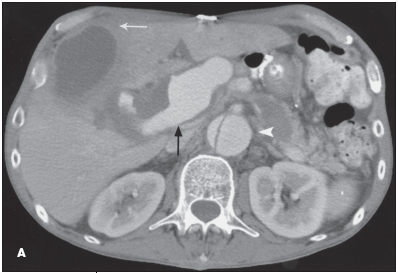

The main factors involved in the pathogenesis of hepatic artery aneurysms are atherosclerosis, medial degeneration, trauma, and infection.